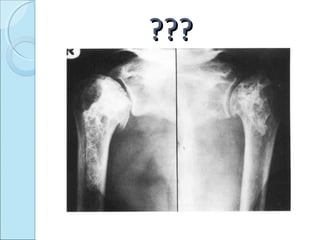

??????

CAISSON DISEASECAISSON DISEASE

 DYSBARIC OSTEONECROSIS.

 exposure to hyperbaric atmosphere.

 Undersea diving ,space craft.

 Result in decompression sickness.

MECHANISMMECHANISM

 Nitrogen bubbles liberated from bone marrow –

bone infarct by small blood vessel occlusion

 Resultant osteonecrosis..

 Shoulder most commonly involved.

RADIOGRAPHIC FINDINGSRADIOGRAPHIC FINDINGS

 Juxta articular defects

transradiant subcortical band.

collapse of articular cortex.

sequestration of articular cortex.

secondary osteoarthritis.

 Neck and shaft lesions

dense areas.

irregular calcified areas.